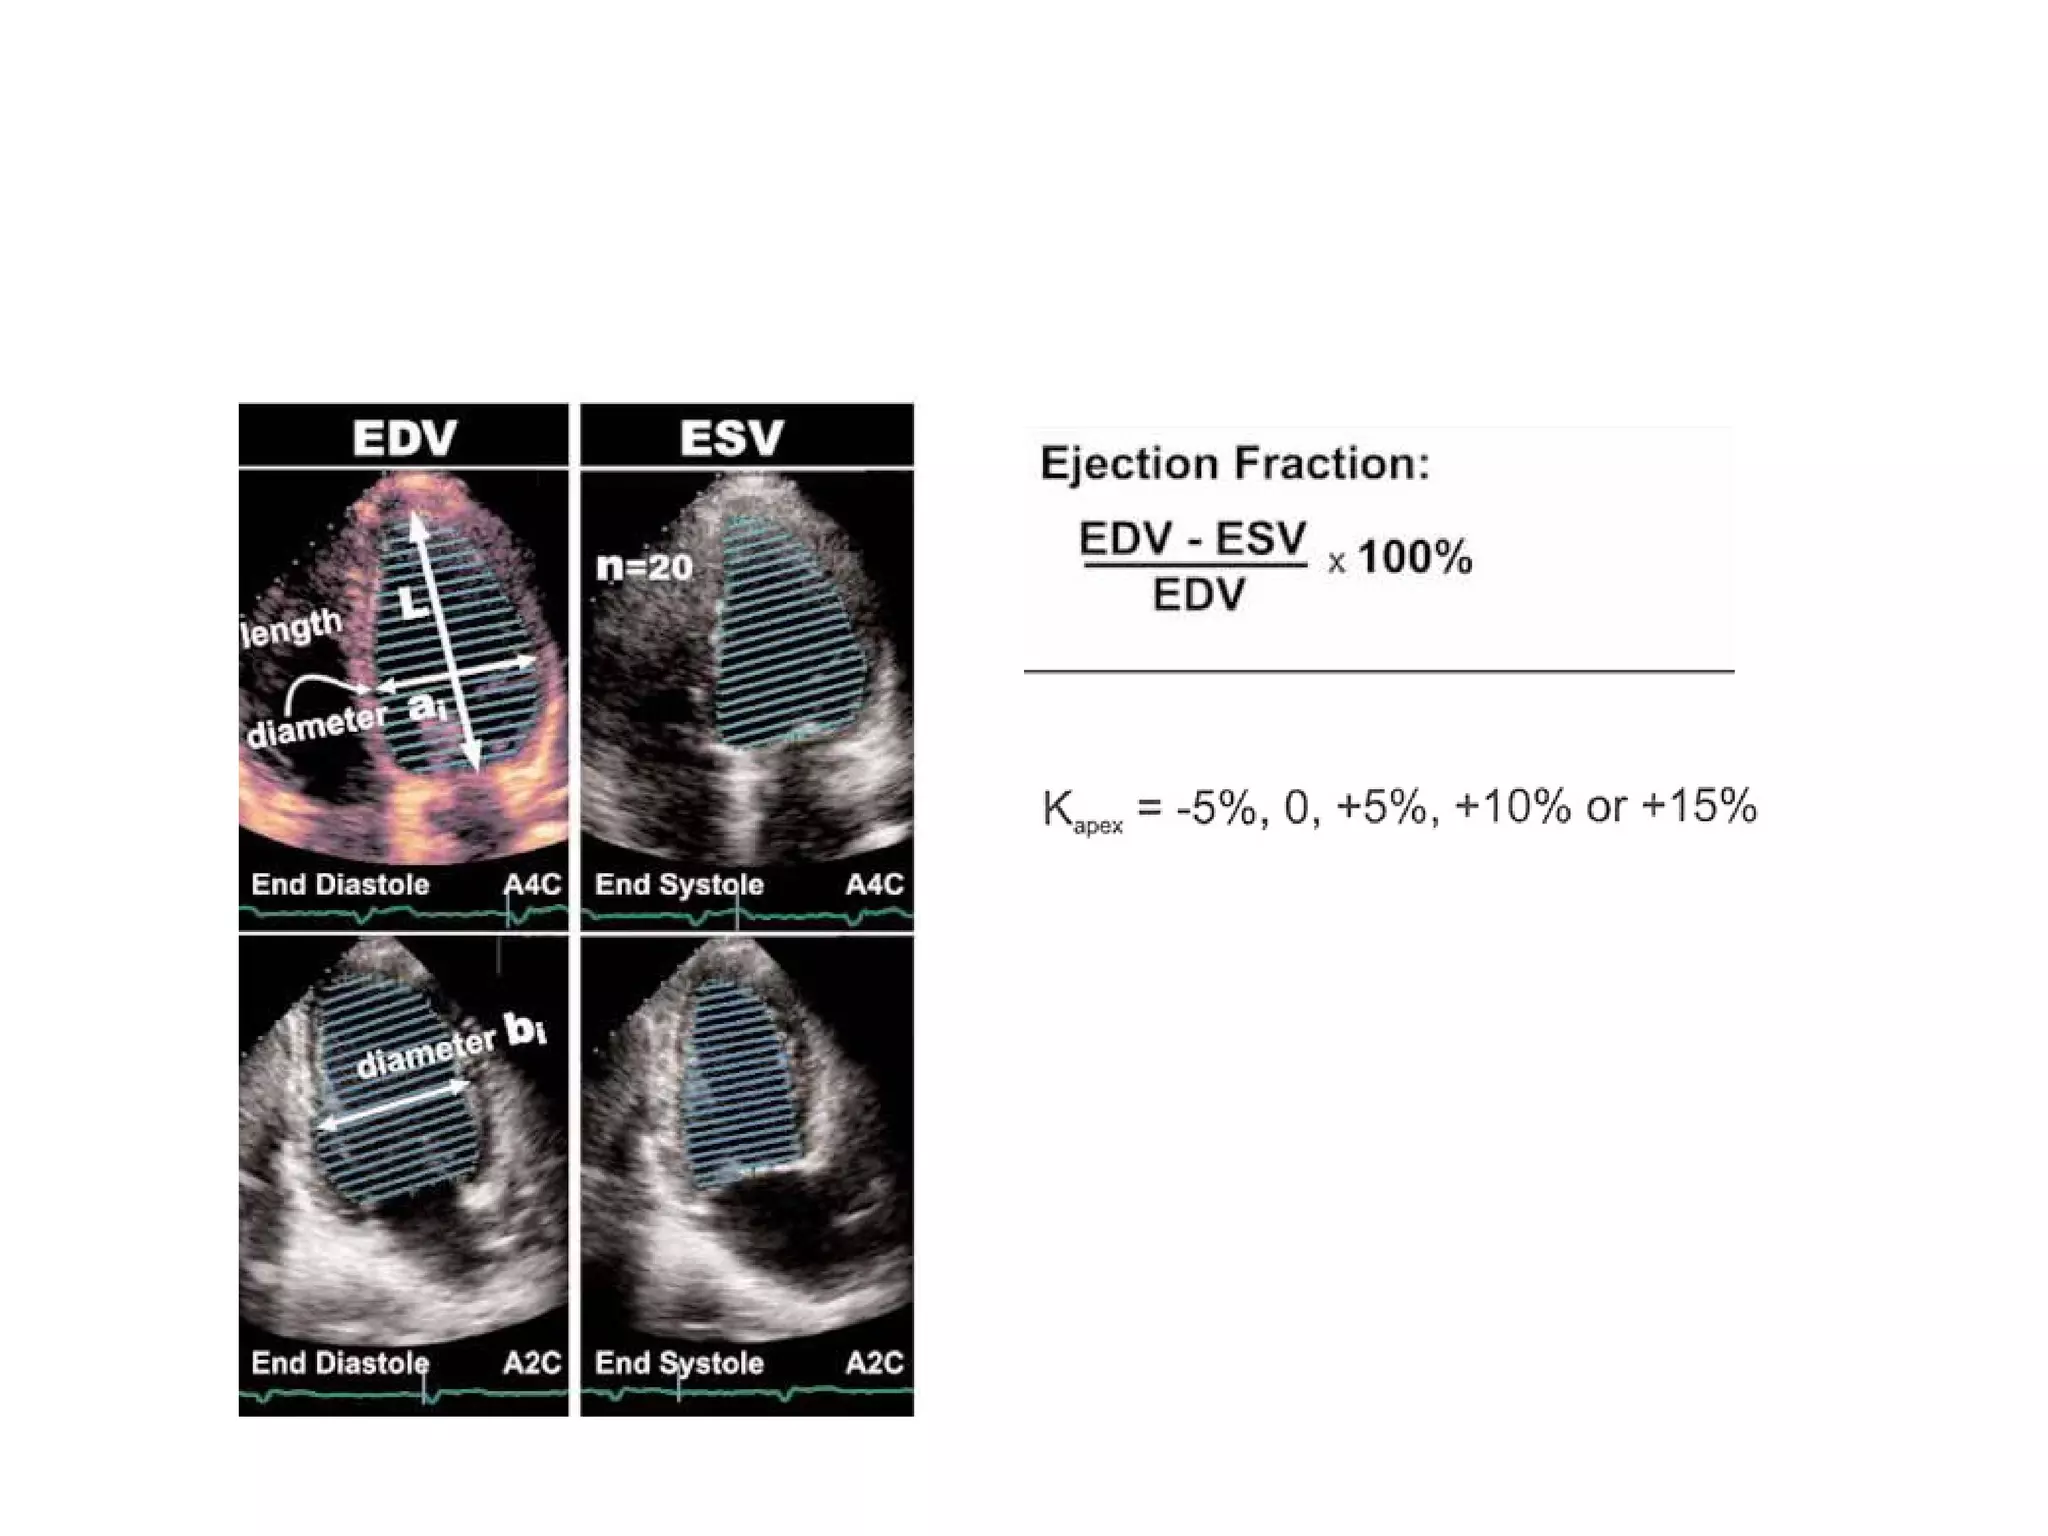

• LV volumes by 2D:

1. Prolate ellipsoid method.

2. Hemi-ellipsoid (bullet) method.

3. Biplane method of discs (modified

Simpson’s)

• Fractional shortening—the % change in

the LV minor axis in a symmetrically

contracting ventricle

• FS(%)= (LVIDd – LVIDs)/LVIDd × 100%

• FS = 25% – 45% (normal range)